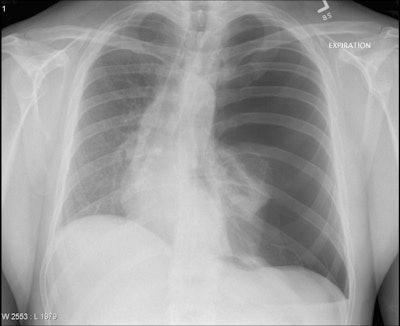

The survey included nine hypothetical clinical vignettes, each associated with a chest x-ray that showed only a single acute chest pathology. For example, a vignette for a patient with dyspnea and pleuritic chest pain contained a classic image of pneumothorax. The researchers further added a low-risk vignette associated with a normal chest x-ray. They asked participants to read each of the 10 vignettes, look at the chest x-rays, and type in the pathology they believed they saw. Also, they asked them to state their confidence in the diagnosis and indicate any prior exposure to the topics.

Overall, the highest rate of correct diagnosis was for diaphragmatic herniation (77%), followed by pneumoperitoneum (67%) and pneumothorax (54%). The lowest rate of correct diagnosis occurred for acute respiratory distress syndrome (ARDS) (8%), foreign body (12%), and the low-risk vignette associated with the normal chest x-ray (15%). The key findings are shown on the table below.

Normal | 15 | 13 | 44 |